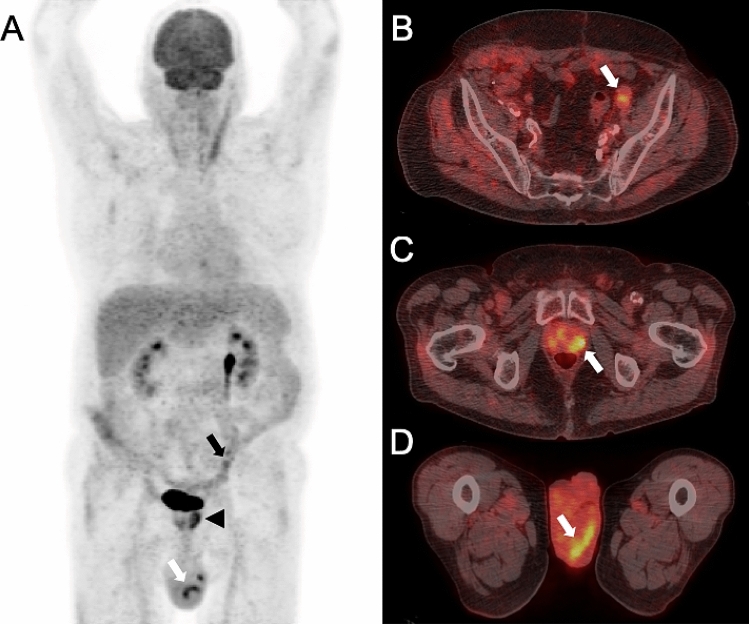

Figure 4.

A 66-year old male patient was referred to PET/CT for follow-up of a vascular graft infection with P. aeruginosa. PET/CT [maximum intensity reconstructions of PET (A) and fused PET/CT images (B–D)] showed intense focal FDG uptake of the aortobifemoral graft (black arrow head in A, white arrow in B), suggestive for persistent infection. Subsequently, the aortobifemoral graft was reconstructed in situ with a SilverGuard Dacron graft. An unknown and potentially relevant incidental finding was detected in the upper thighs with intense focal FDG uptake, in line with septic emboli (black arrows in A, white arrow in C and D). The incidental PET/CT finding was rated not to have impact on patient management, since no direct action was initiated with regard to the potential septic emboli in the upper thighs.